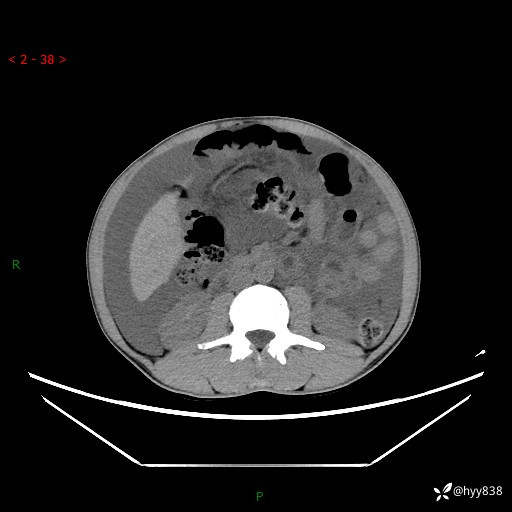

现病史:患者10天前无明显诱因出现腹部胀痛不适,无畏寒发热,无胸痛胸闷,无心慌气短,无恶心呕吐,无腹泻及黑便,无粘液血便及里急后重等症状,4天前在当地县人民医院就诊,行腹部CT示:下腹部占位性病变,腹腔及盆腔积液;今患者为求进一步诊治来我院治疗,门诊以“腹水”收治入院。 发病以来,精神饮食可,大小便正常,体重体力无明显变化。

腹部CT平扫+增强